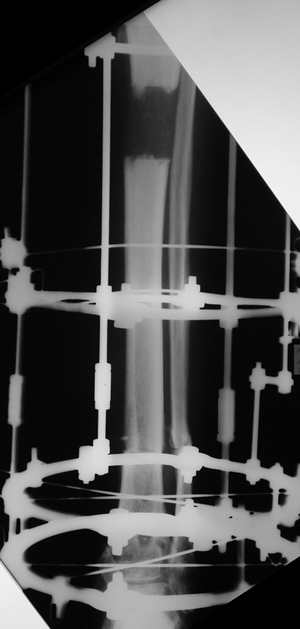

Еще один пример.

Мужчина, 33 года, резекция б\б кости по поводу остеомиелита после открытого перелома. Стандартная методика билокального остеосинтеза (рис 1 и 2). В конце удлинения выявилось неудовлетворительное взиморасположение перемещенного фрагмента и дистального отломка (рис 3). Планирование (рис 4).

Адаптация отломков гексаподом за 5 дней (рис 5). Замена гексапода на обычные штанги (рис 6 и 7)